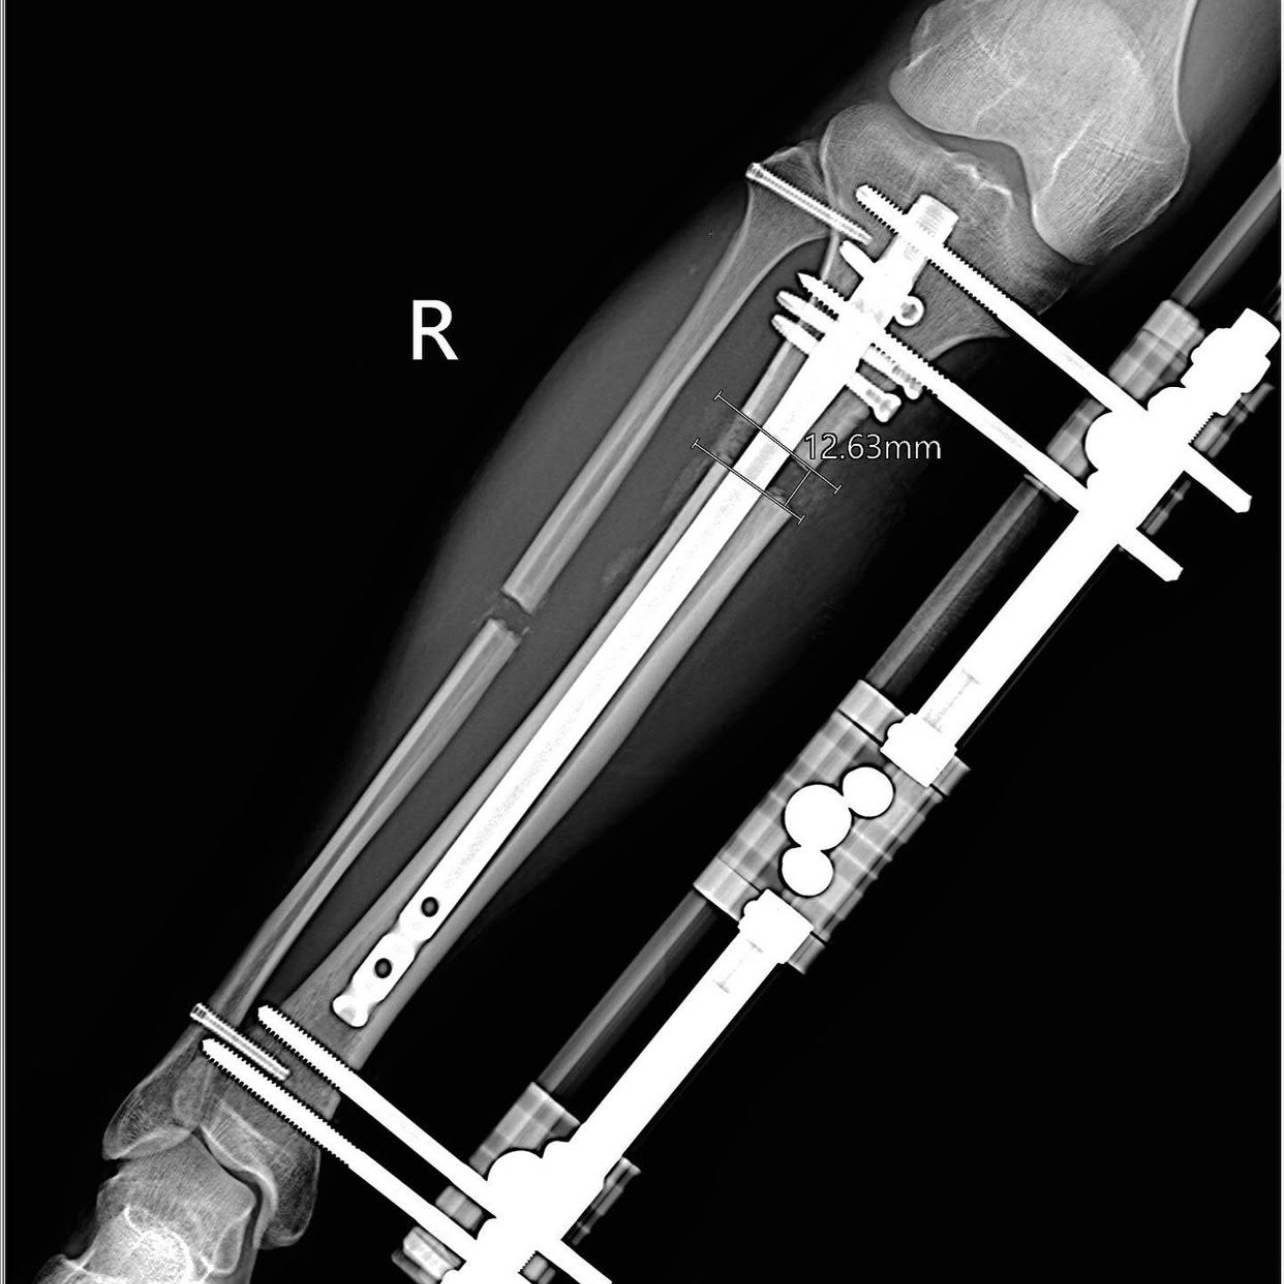

胫骨肢体延长手术动画